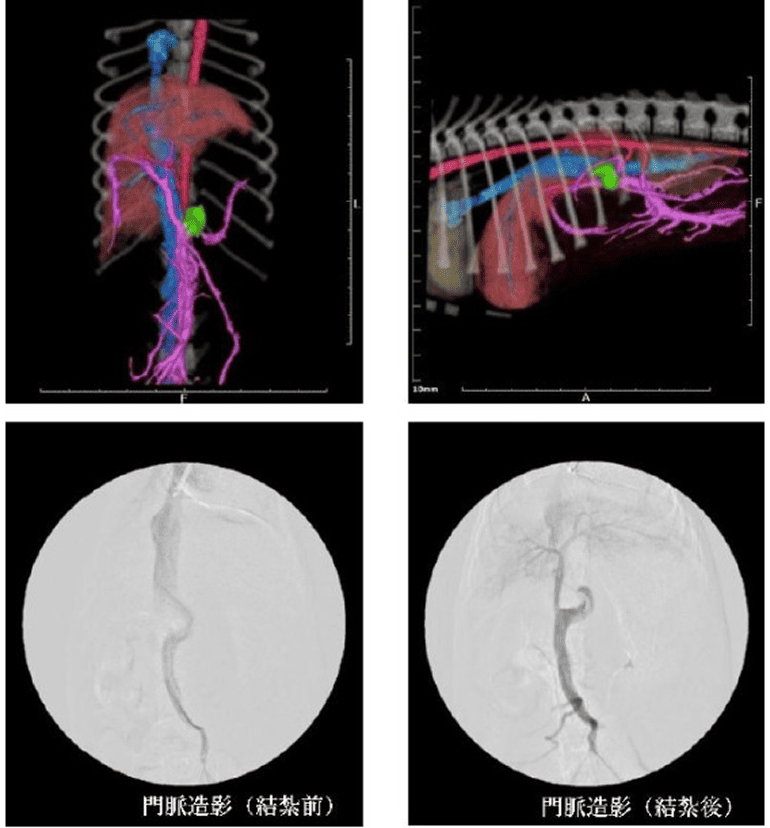

門脈シャント

肝細胞癌の動脈塞栓術・インスリノーマの動脈塞栓術・脳腫瘍術前止血・門脈シャント形成術・抗癌剤動注リザーバー療法・胆管ステント・子宮平滑筋腫の動脈塞栓術

大腿動脈からカテーテルを挿入し、X線透視下で、肝動脈に進めていきます。

造影剤を用いて肝動脈の全体像や腫瘍の位置を確認し、腫瘍の栄養血管を確認します。カテーテルの中にマイクロカテーテルを挿入します。

目標とする腫瘍の栄養血管へ造影剤を注入し、腫瘍のみが造影されることを確認した後に、塞栓物質を投与し栄養血管を塞栓させます。栄養血管が複数存在する場合は、同様の処置を繰り返します。

治療実施から107日の時点で、腫瘍の明らかな縮小が認められた。

一般状態は安定し経過良好であった